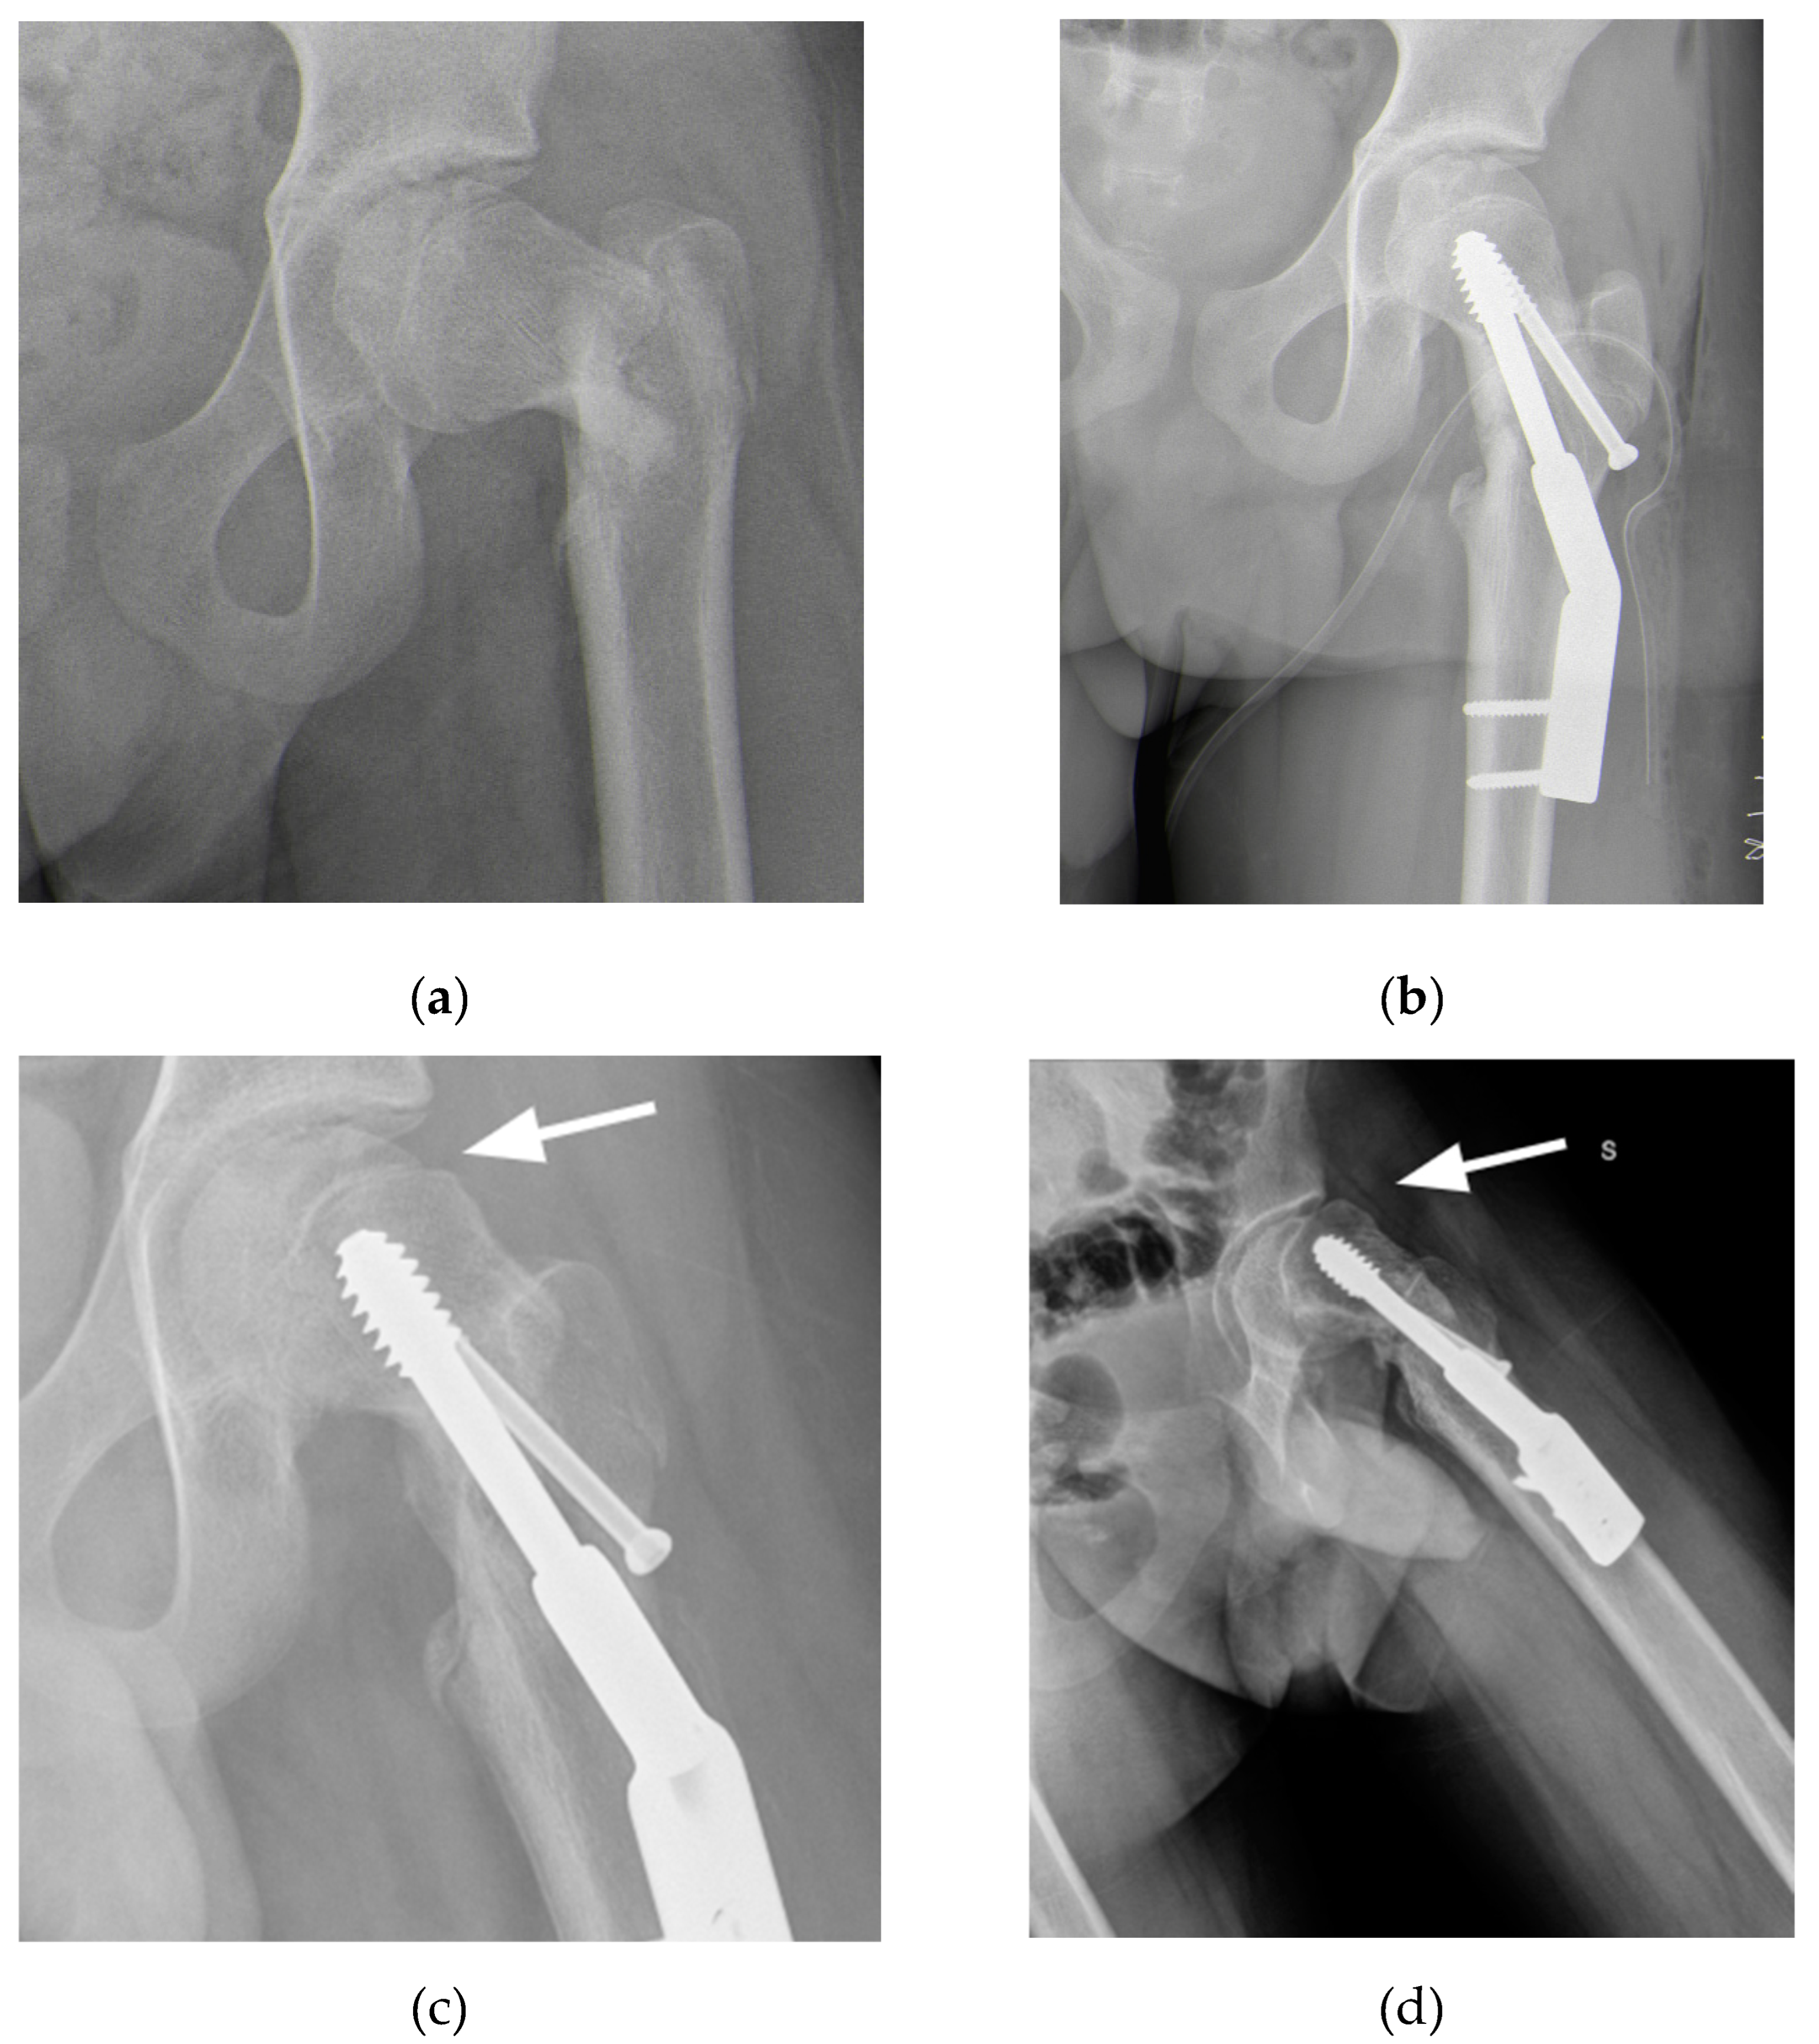

3. Results

The surgery was performed without any complication. Blood loss was 500 mL, the number of fluoroscopic images was 41 (cumulative dose 72.7 cGy/cm2), the surgical time was 176 minutes. At the last follow-up, 6 months postoperatively, the patient had resumed walking, although with difficulties in following the rehabilitation program due to his autism. The hip is highly mobile and pain-free. Radiographs showed good consolidation with no signs of AVN of the femoral head (Figure 10).

Figure 10. Radiographs at 6 months follow-up (a) Antero-posterior view; (b) Frog-leg view.